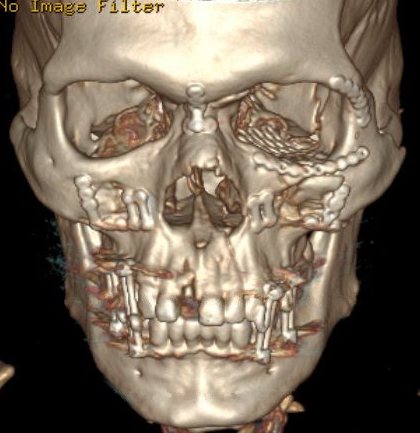

- Accurately identify fractures using CT and 3DCT radiographic findings to prescribe the appropriate treatment required for midface and zygoma fractures.